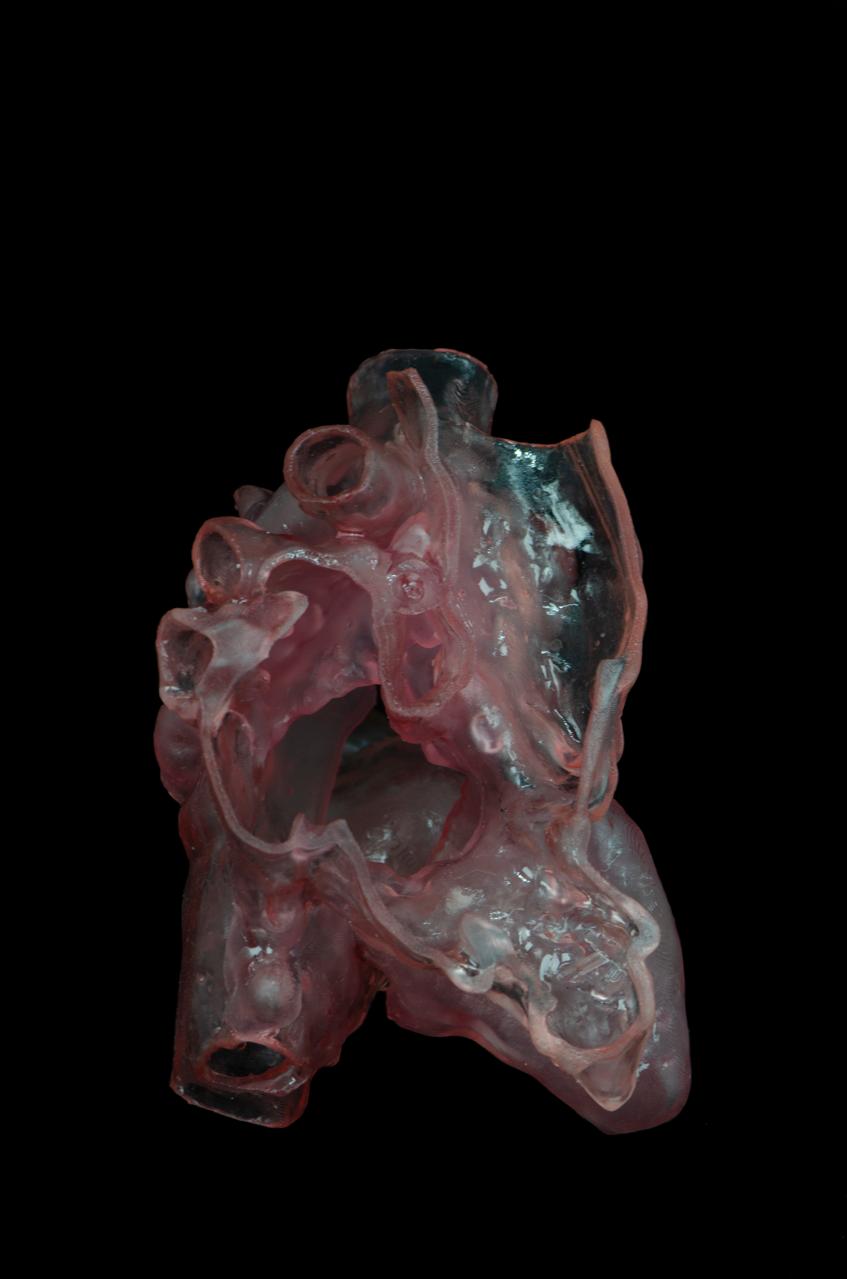

The technology follows a precise scientific process that begins with evaluating the patient’s condition using cardiac images obtained through ultrasound scans (echocardiography). In more complex cases, high-resolution computed tomography (CT) scans of the heart are used. These images are then processed using specialized software and transformed into tangible physical models that accurately reflect the true anatomy of the affected child’s heart.

The printed model allows surgeons to examine internal details and anatomical relationships between the different parts of the heart with exceptional accuracy, including valve anatomy, the pathways of the major arteries, and the precise location of cardiac defects. This is reflected in improved outcomes during surgery.

In the treatment of congenital heart disease, 3D printing enables physicians to gain a highly accurate understanding of the patient’s complex cardiac anatomy by creating a three-dimensional model identical to the real heart. This helps cardiologists and surgeons plan the procedure in advance and choose the best approach for repairing the defects, increasing the chances of achieving a complete repair rather than resorting to palliative procedures that do not provide a definitive cure. The technology also contributes to better surgical outcomes, fewer complications, and an improved quality of life for patients in the long term.